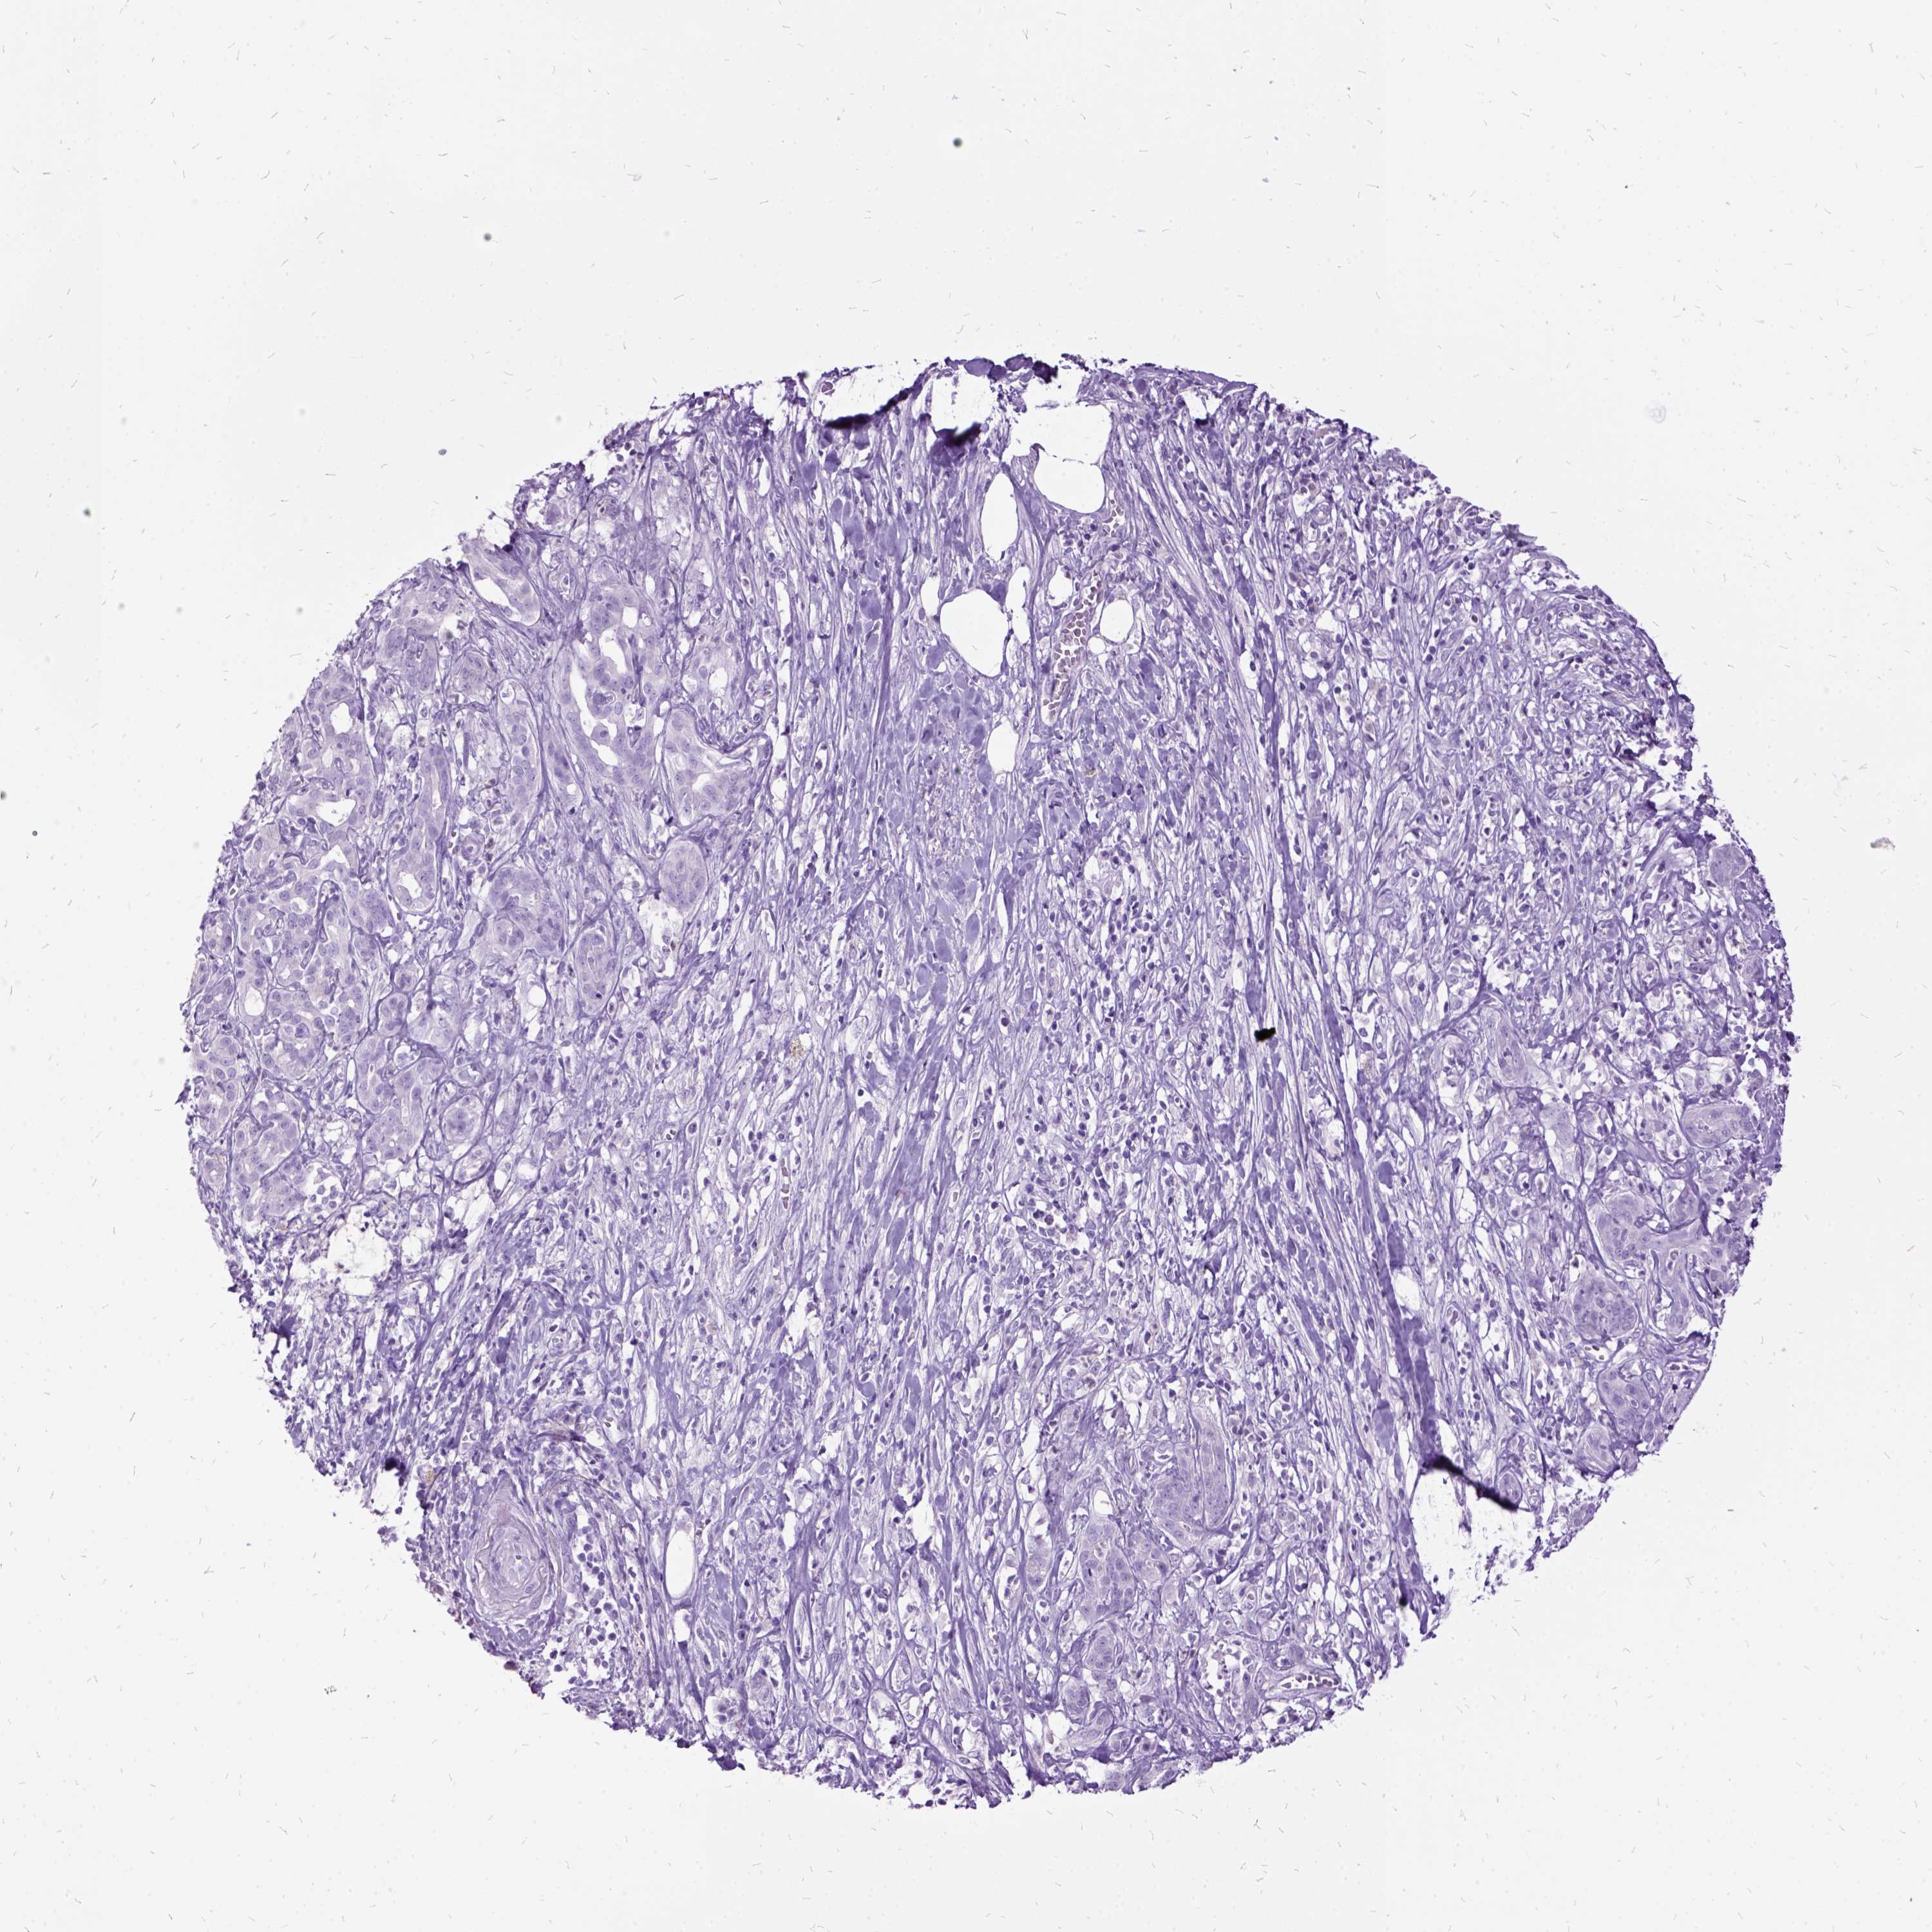

PANCREATIC CANCER - Protein expressioni

A mouse-over function shows sample information and annotation data. Click on an image to view it in a full screen mode. Samples can be filtered based on level of antibody staining by selecting one or several of the following categories: high, medium, low and not detected. The assay and annotation is described here.

Note that samples used for immunohistochemistry by the Human Protein Atlas do not correspond to samples in the TCGA dataset.

Antibody stainingi

Antibody staining in the annotated cell types in the current human tissue is reported as not detected, low, medium, or high, based on conventional immunohistochemistry profiling in selected tissues. This score is based on the combination of the staining intensity and fraction of stained cells.

Each image is clickable and will lead to virtual microscopy that enables deeper exploration of all samples and also displays staining intensity scores, fraction scores and subcellular localization as well as patient and tissue information for each sample.

Antibody HPA052583

Antibody HPA056072

Antibody CAB000013

Adenocarcinoma, NOS